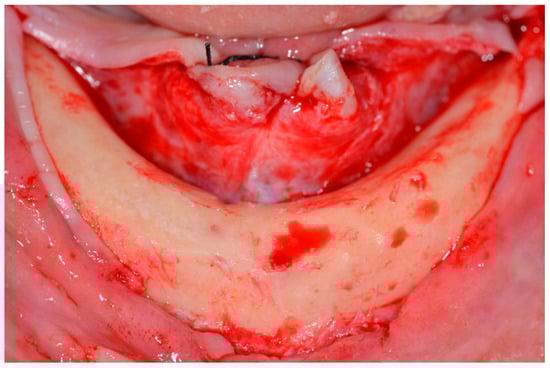

A supra-crestal incision was made in the first molar region, and two vertical releasing incisions were made in the first molar region. A mucoperiosteal flap was made and deflected, allowing the anatomical structures to be visualized [19] (Figure 3).

Figure 3.

View of the mandible after elevating the mucoperiosteal flap.